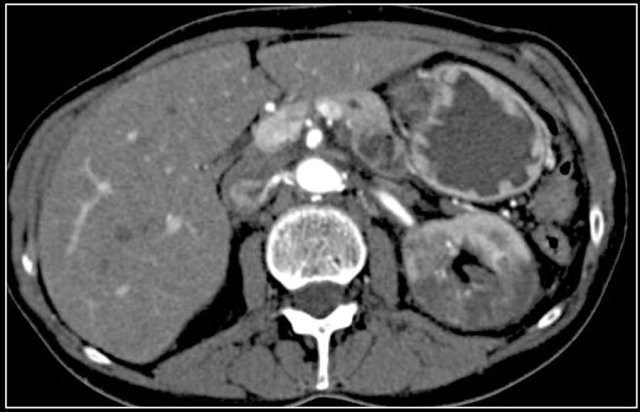

In this case there are hypodense areas in both kidneys.

Based on the imaging alone the main differential is multifocal pyelonephritis, lymphoma and metastases.

This patient had a urinary tract infection and episodes of flank pain and there was no history of a primary tumor or lymphoma.

So the diagnosis is pyelonephritis.

A CT scan 4 months later shows normal enhancement of both kidneys; the renal abnormalities on the first scan were therefore consistent with an episode of multifocal pyelonephritis.